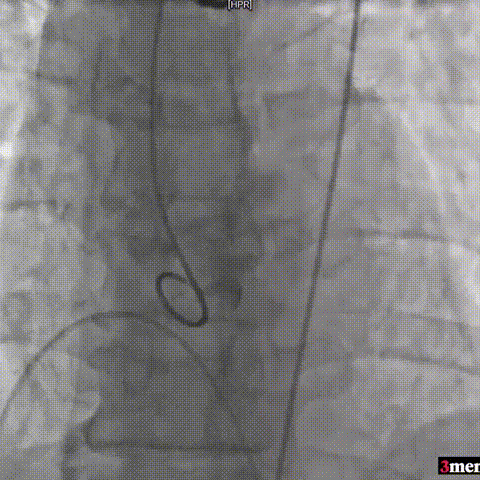

手术过程回顾:

主动脉根部造影

直头导丝跨瓣

球囊预扩

输送器过弓

瓣膜定位

瓣膜释放至工作位

瓣膜脱钩

球囊后扩

术后超声提示患者跨瓣压差即刻显著下降,反流量轻微。术中未出现相关并发症,术后患者心功能持续得到改善,效果良好,圆满取得此次手术成功。